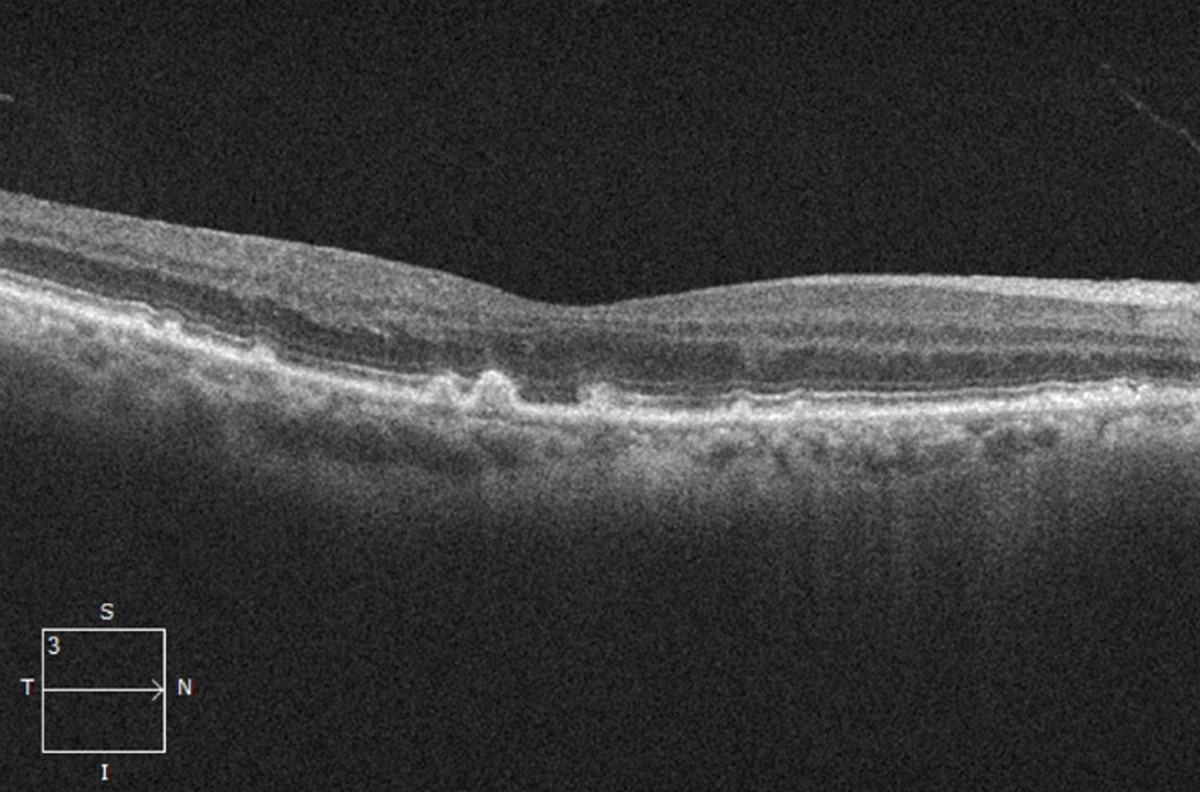

The presence of drusen and retinal pigment epithelium changes characterize non-neovascular or nonexudative—dry—AMD in the absence of neovascularization (Figure 1). Historically, the Age-related Eye Disease Study classified dry AMD based on examination findings of hard drusen, soft drusen, RPE abnormalities and atrophy.1

| Figure 1. Optical coherence tomography scan showing drusen (accumulation of deposits underneath the retinal pigment epithelium), a sign of dry age-related macular degeneration. |